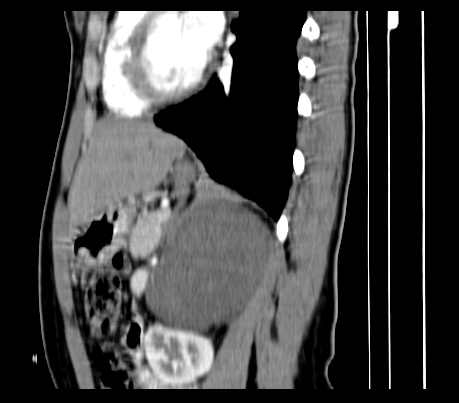

静脉期

延时5分钟